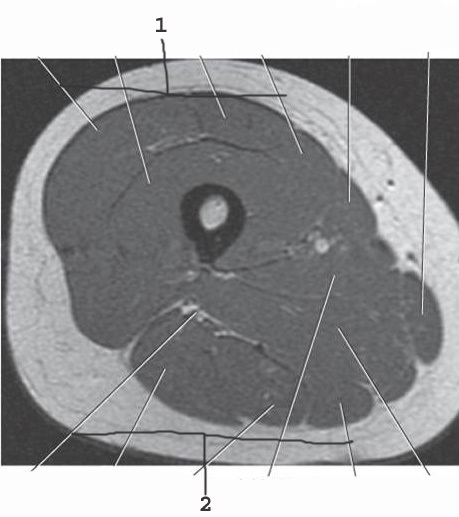

1

Quadracep group

2

hamstring group